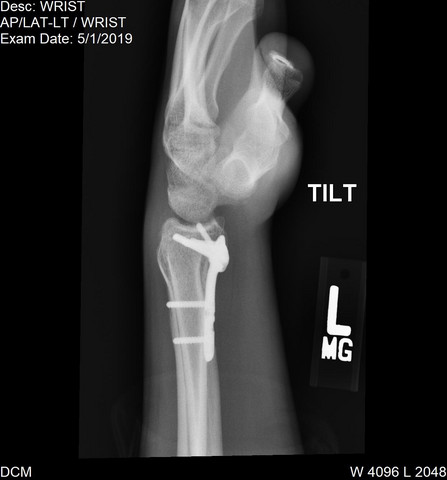

Platte aus handgelenk entfernen wie lange krank. Bevor das Material entfernt werden kann muss der knöcherne Heilungsprozess vollständig abgeschlossen sein dies kann der Arzt auf dem Röntgenbild erkennen. 10 Tagen werden die Wundfäden entfernt. Die Heilungszeit des Knochens und der Weichteile beträgt allerdings in den meisten Fällen mindestens 3 4 Monate gelegentlich auch über 6 Monate bis Vollbelastung möglich ist.

Kommt es durch voluminöse Platten durch vorstehende Schraubenköpfe oder überlange Schrauben zu einer direkten Sehnenschädigung oder durch eine Fehllage der Schrauben zu einer Behinderung der Gelenkbeweglichkeit muss das gesamte Material vorzeitig entfernt werden. 2 wochen krankschreiben würde wenn er sich seine platten und schrauben die er so im körper hat entfernen lassen würde. Versuchen alles sofort wieder zu bewegen.

Hierbei wird ein 2-3 mm langer Keil aus der Elle entnommen und die Elle in verkürzter Position mit einer Platte stabilisiert. Direkt nach der Operation sowie nach acht Wochen wird der Bruch im Röntgenbild kontrolliert. Unser hausarzt der auch chirug is aber nur ambulante kleinere ops durchführen darf meinte mal zu meinem bruder dass er ihn ca.

Ich hab meine Platte im Handgelenk auch nach 8 Monaten entfernen lassen raus mit dem Fremdkörper. Die Entfernung des Metalls stellt einen kleinen Eingriff dar als der der bei der ursprünglichen Operation notwendig war.

Distale Radius Fraktur Platte Schrauben Rontgenbild Gesundheit Und Medizin Gesundheit Operation